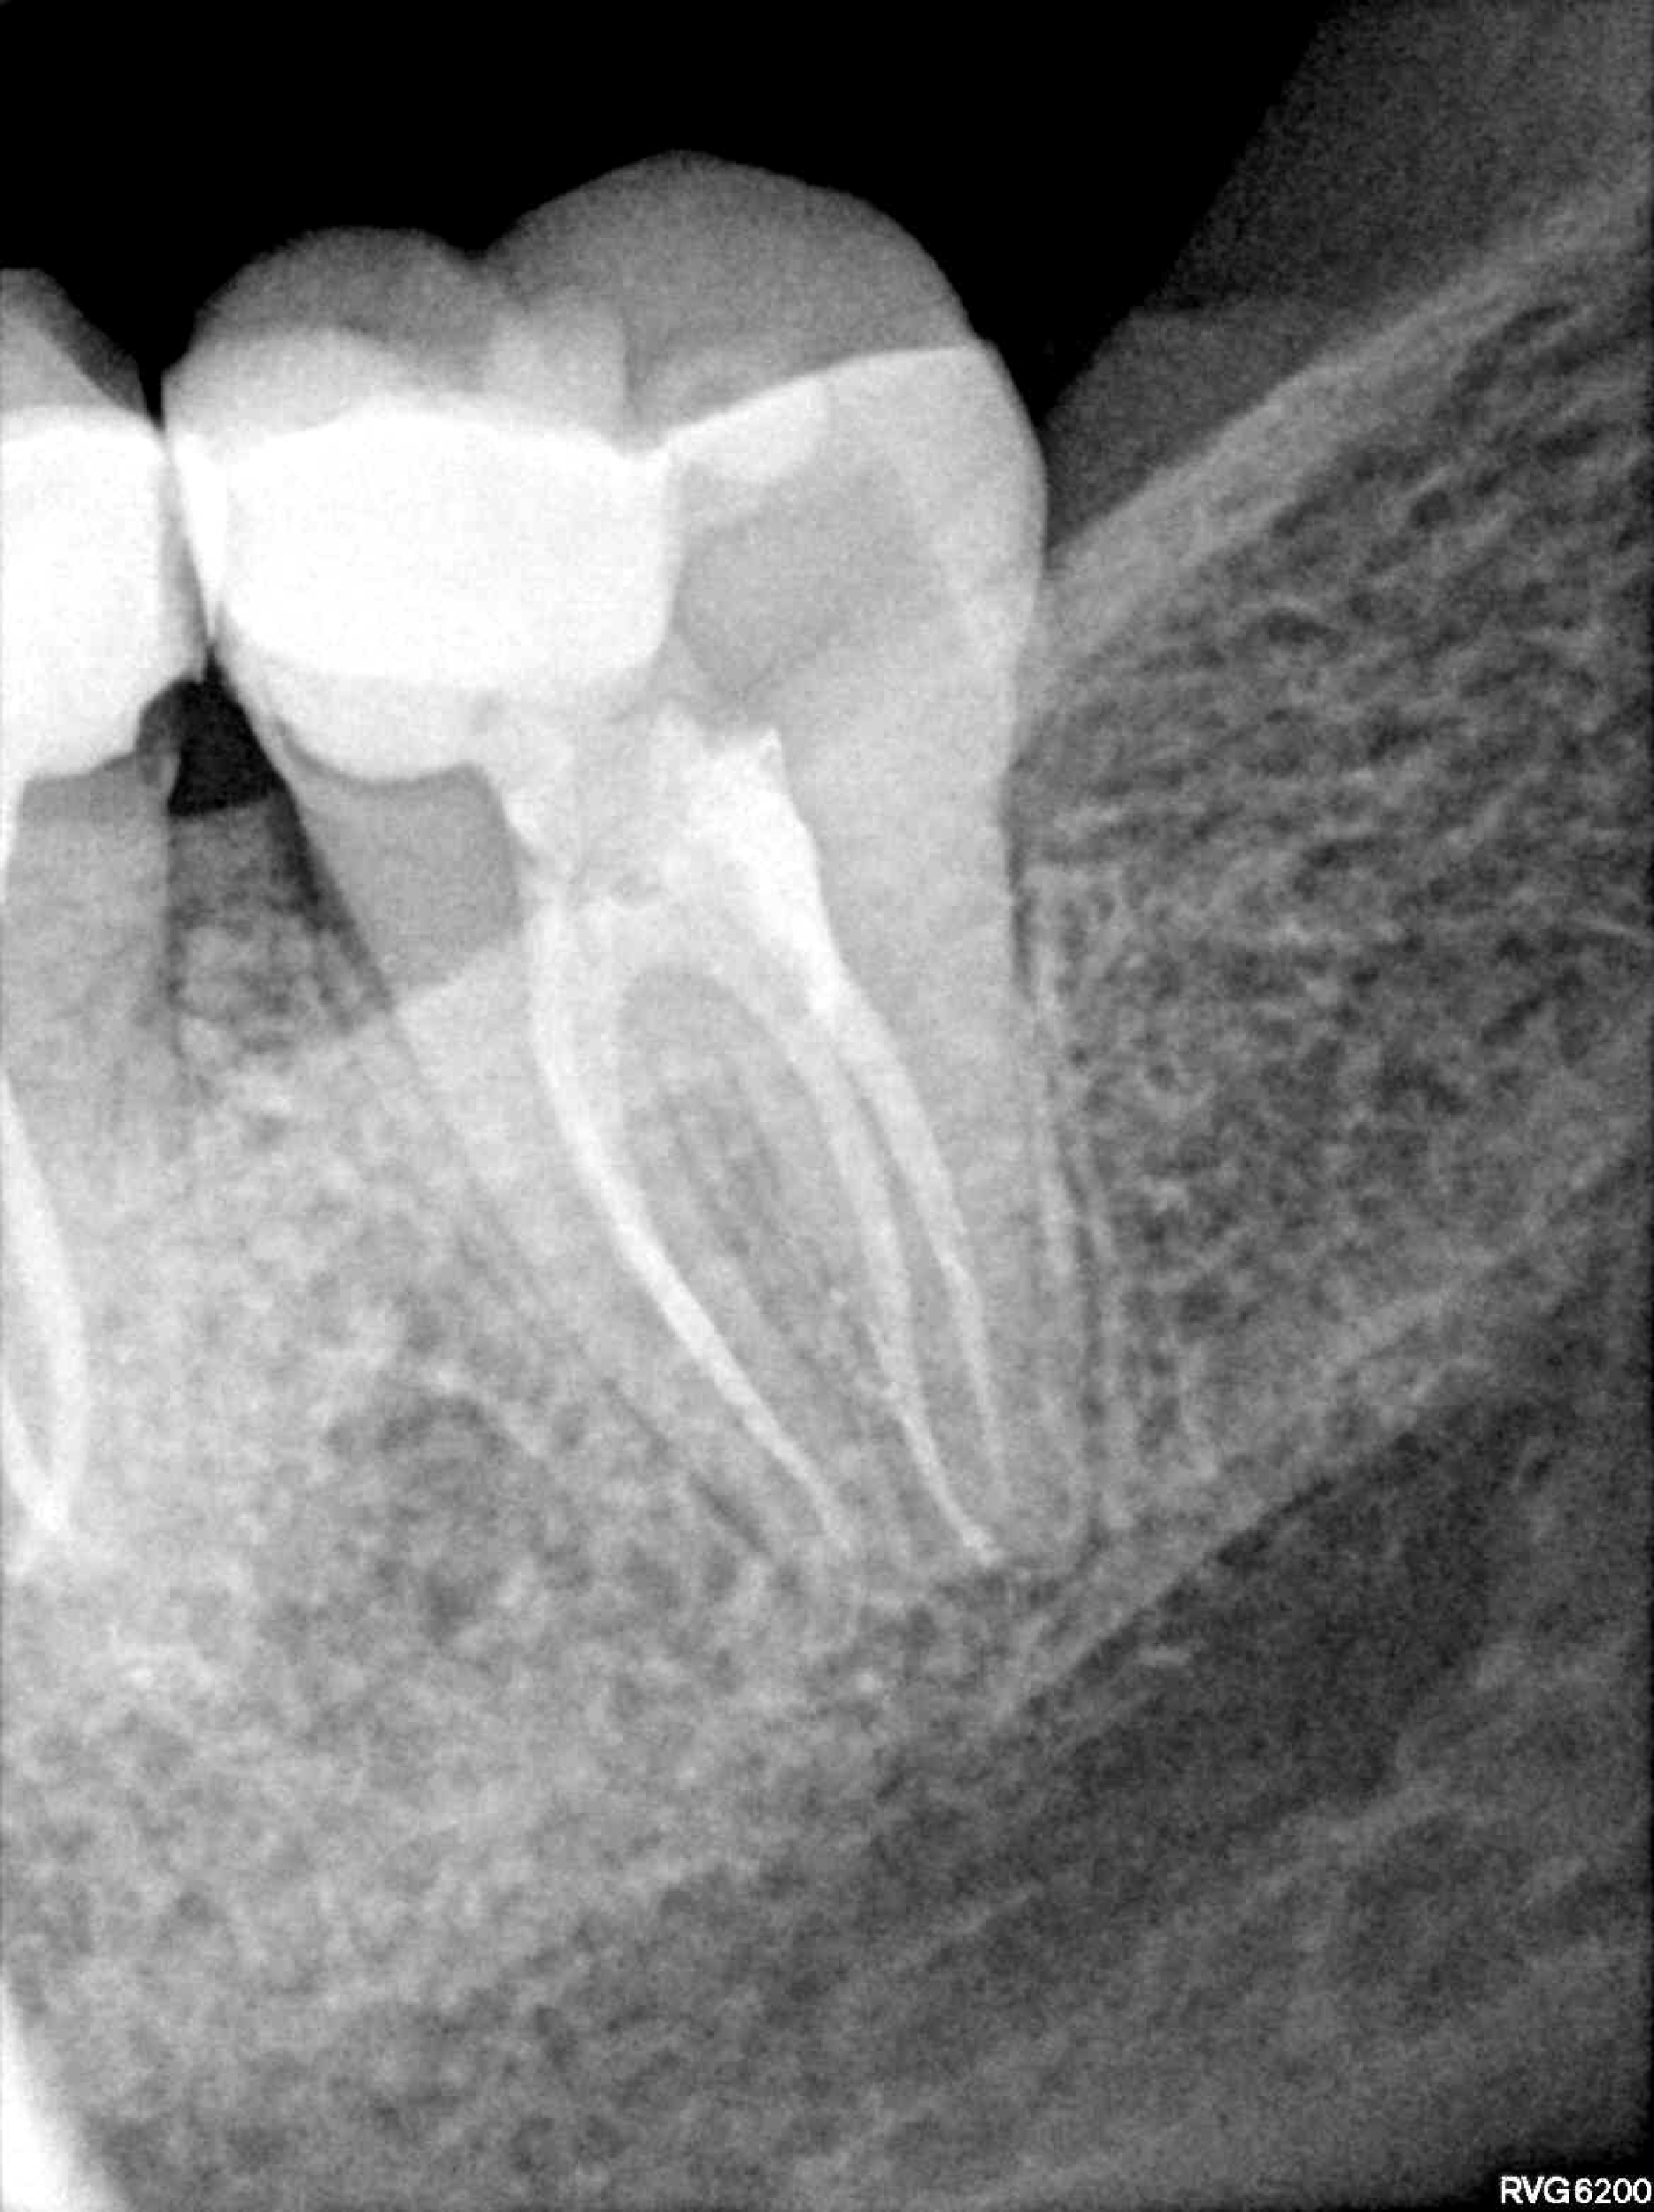

Categoría Endodoncia

Radiografías

Imágenes del tratamiento